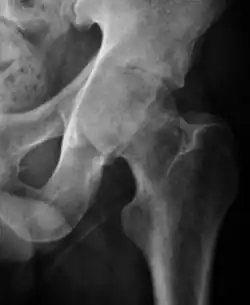

Plain radiography allows us to categorize the hip as normal or dysplastic or with impingement signs (pincer, cam, or a combination of both). Besides these, pathologic processes like osteoarthritis, inflammatory diseases, infection, or tumors can also be identified (Figure 1).[1]

Figure 1.

Radiography in normal hip

In adults, one of the main indications for radiographs is the detection of osteoarthritic changes (Figure 1(e)). Nevertheless, radiographs usually detect advanced osteoarthritis that can be graded according to the Tönnis classifications. The grading system ranges from 0 to 3, where 0 shows no sign of osteoarthritis. Intermediate grade 1 shows mild sclerosis of the head and acetabulum, slight joint space narrowing, and marginal osteophyte lipping. Grade 2 presents with small cysts in the femoral head or acetabulum, moderate joint space narrowing, and moderate loss of sphericity of the femoral head. Grade 3 is the severest form of osteoarthritis, which manifests as severe narrowing of the joint space, large subchondral cyst with productive bone changes that may lead to deformity of the bone components of the joint, while secondary osteoarthritis due to calcium pyrophosphate deposition can be diagnosed when calcification of hyaline cartilage and fibrocartilage is detected.[1]